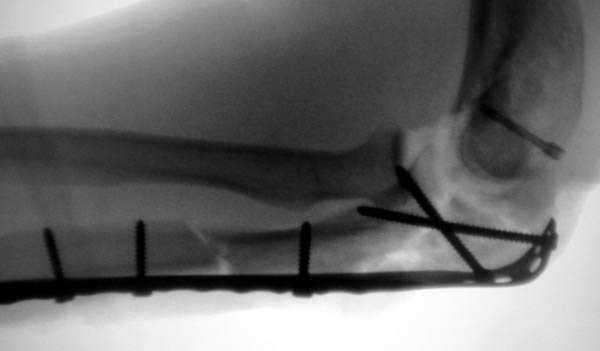

Здесь выставлены несколько случаев и варианты фиксации локтевого отростка, некоторые в комбинации с другими переломами.

3 вариант

перелом с capitelum humerus и проксимальной трети улна